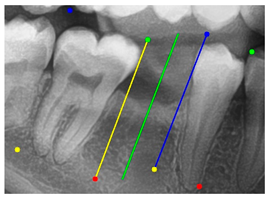

| YOLO-OBB result | ||||||

| Validation Image 1–6 | ![]() | ![]() | ![]() | ![]() | ![]() | ![]() |

| Accuracy | 84.13% 75.18% | 90.29% 76.49% | 87.38% 87.27% | 80.40% 84.48% | 70.11% 83.41% | 88.46% 76.33% |

| AI-assisted and implant path visualization result | ||||||

| Comparison with dentist’s ground truth (black line) and our framework (green line) | ||||||

| MSE | 3.59 | 1.29 | 0.41 | 0.80 | ||